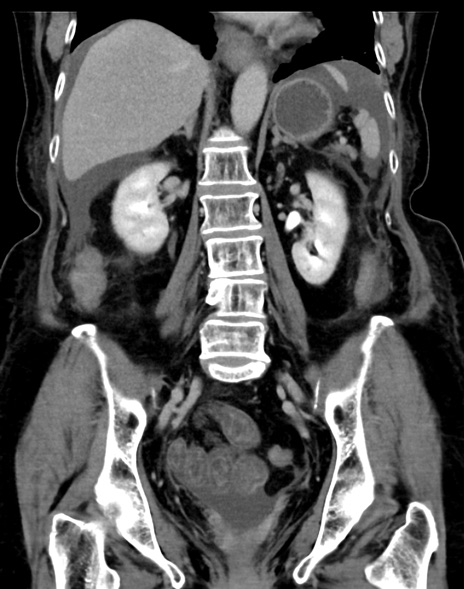

症例13 CT(冠状断像)1日半後